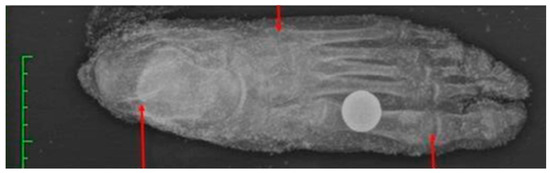

Radiological investigations were carried out to exclude the presence of gunshot ammunition material, to exclude further microfractures and to determine the degree of fusion of the ossification nuclei (Figure 6) and, finally, several soft tissue samples were taken, where possible, for histological and genetic investigations. The samples taken were subjected to DNA extraction using the commercial NucleoSpin®DNA Tissue kit from MACHEREY-NAGEL, following the specific protocol indicated by the manufacturer.

Figure 6. Analysis of the degree of fusion of ossification nuclei of the proximal epiphysis of the femur and humerus.